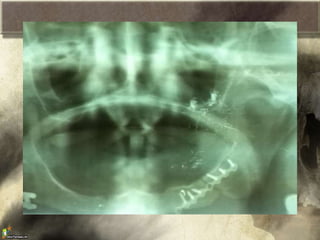

Fracturas de Maxilar inferior

• Al fracturarse la mandibula se producen 3

zonas distintas:

– Tension

– Neutra

– Presion

• La accion de los musculos masticadores

pueden “ayudarnos” a que no se desplaze la

fractura, o puede perjudicarnos dependiendo

del trazo

• Diagnostico sugerido por:

– Maloclusion

– Dolor

– Edema

– Equimosis

– Hematoma

– Deformidad

– Hematoma sublingual

– Crepitación a la tracción

– “Halitosis y sialoreha”

– Hipoestesia mentoniana

• Fracturas de condilo unilateral, dolor

preauricular y desviación contralateral

Fracturas de Maxilarinferior • Al fracturarse la mandibula se producen 3 zonas distintas: – Tension – Neutra – Presion • La accion de los musculos masticadores pueden “ayudarnos” a que no se desplaze la fractura, o puede perjudicarnos dependiendo del trazo

• Diagnostico sugeridopor: – Maloclusion – Dolor – Edema – Equimosis – Hematoma – Deformidad – Hematoma sublingual – Crepitación a la tracción – “Halitosis y sialoreha” – Hipoestesia mentoniana • Fracturas de condilo unilateral, dolor preauricular y desviación contralateral